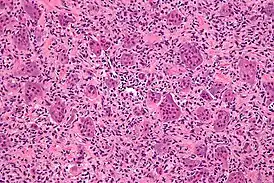

![]() Микрофотография гигантских клеток остеобластокластомы кости, характерно выделяются гигантские клетки. Окрашено гематоксилином и эозином. | |

Микроскопическая структура гигантоклеточной опухоли кости, в основном, представлена двумя типами клеток. Преобладающее большинство клеточных элементов составляют веретенообразные, овальные и округлые клетки с умеренно выраженной цитоплазмой и светлым ядром, содержащим небольшое количество хроматина. В ядрах определяются одно, а иногда два хорошо различимых ядрышка, могут выявляться фигуры митоза, как правило, типичные.

Другим клеточным компонентом являются многоядерные гигантские клетки. Эти клетки очень похожи на нормальные остеокласты, но обычно несколько крупнее их и имеют закругленный контур. Они содержат 20-30 и более ядер, большинство из которых располагаются в центре клетки. Ядра многоядерных клеток обычно лежат изолировано друг от друга и, практически, не отличаются от ядер одноядерных клеточных элементов. Цитоплазма этих клеток слегка базофильна. В многоядерных гигантских клетках фигур митоза не определяется. Эти клетки равномерно (важный дифференциальный диагностический признак!) расположены в опухоли.